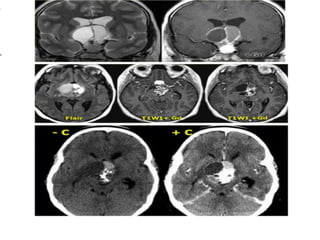

The following case concerns a 9-year-old male with a history of headache, nausea and vomiting. Sagittal T1 images

before and after intravenous contrast show a mass in the midline, on the floor of the third ventricle. The mass

enhances after gadolinium. Continue with next images. Sagittal T2 and T1WI . This is a Germinoma.

Figure 16: Sagittal (A) and (B) T1 weighted enhanced images of two different germinomas. (A) demonstrates a large

homogeneously enhancing soft tissue mass within the suprasellar region involving the upper aspect of the pituitary stalk and

the hypothalamic region with a second separate mass visible in the region of the pineal gland -this is typical of a germinoma.

(B) demonstrates a much smaller lesion in the region of the upper aspect of the stalk and hypothalamus (arrow).